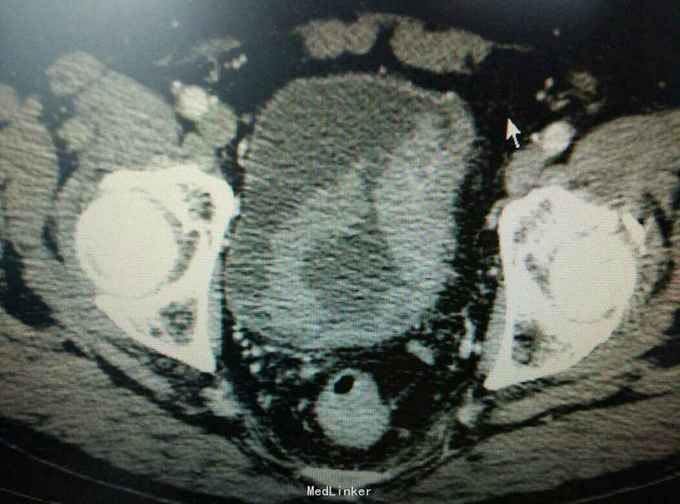

患者三年前无明显诱因下出现无痛性肉眼血尿,单位体检发现膀胱肿瘤,因心里恐惧,未就诊,三年期间患者阅读了日本作者近藤诚的著作不要再上肿瘤的当等书籍,拒绝治疗,希望与肿瘤共存,三年间反复血尿,最后是血红蛋白剩40g时候发生缺血性心脏病时候住院,反复劝导后同意治疗,活检报告浸润性尿路上皮癌,患者拒绝全膀胱,接受电切治疗。

行膀胱肿瘤电切术,术后常规灌注吡柔比星30mg,术后三月时再次行诊断性膀胱肿瘤电切术,术中未见复发,至今已九个月未见复发